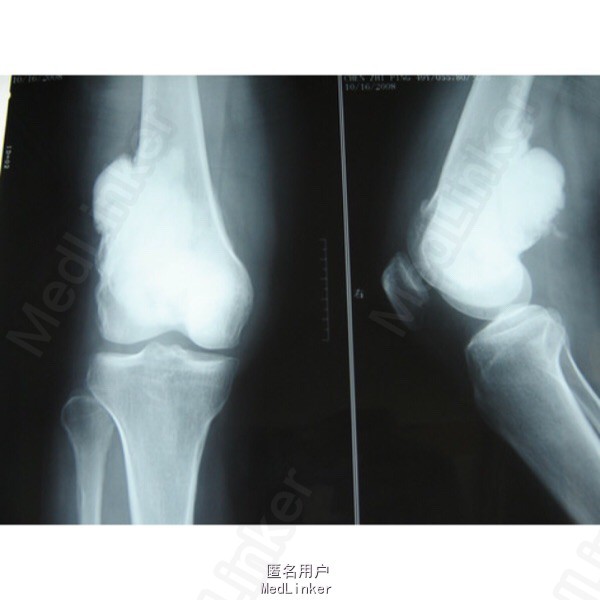

主诉: 左下肢渐进性包块伴疼痛半年。 病史: 左下肢膝关节上端半年前隐痛,逐渐加重,且肿胀有肿块形成,夜晚疼痛剧烈影响睡眠,用药不能缓解,病情发展快,症状表现严重,门诊收入院治疗。

查体: 左膝上肿大,表皮发红,可見有怒张的皮下静脉,触及质硬,无话动性皮肤温度高,压触痛明显,膝关节伸屈活动受限,腹股沟淋巴结未明显触及。 辅助检查: x线检查左股骨下端高密度肿瘤影,环绕股骨周围,硬化,界限尙清,瘤体增生性改变,无骨膜反应。

诊断: 左股骨下端骨皮质旁肉瘤 处理: 瘤段切除、异体骨移植

随访: 随访二年,肿瘤未复发, 讨论: 该肿瘤系骨肉瘤一个类型,恶性程度较低,及时彻底切除肿瘤,是治疗的主要目的,该病例采取瘤段切除,异体骨重建肢体,收到较理想结果。